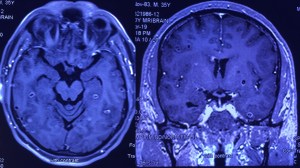

Disseminated cysticercosis (tapeworm) in a vegetarian male

A 35-year-old vegetarian man presented with a generalized convulsion. MRI brain showed extensive cysticerci lesions involving the bilateral supra and infra-tentorial brain parenchyma, myofascial planes of the face, neck, floor of mouth, parotid glands and left orbital extraocular muscles (figure 1). MRI thigh showed diffuse cysticerci involving multiple muscles (figure 2). Disseminated cysticercosis can occur in vegetarians and non-pork eaters due to fecal-oral contamination of food with Taenia solium eggs from tapeworm carriers1.